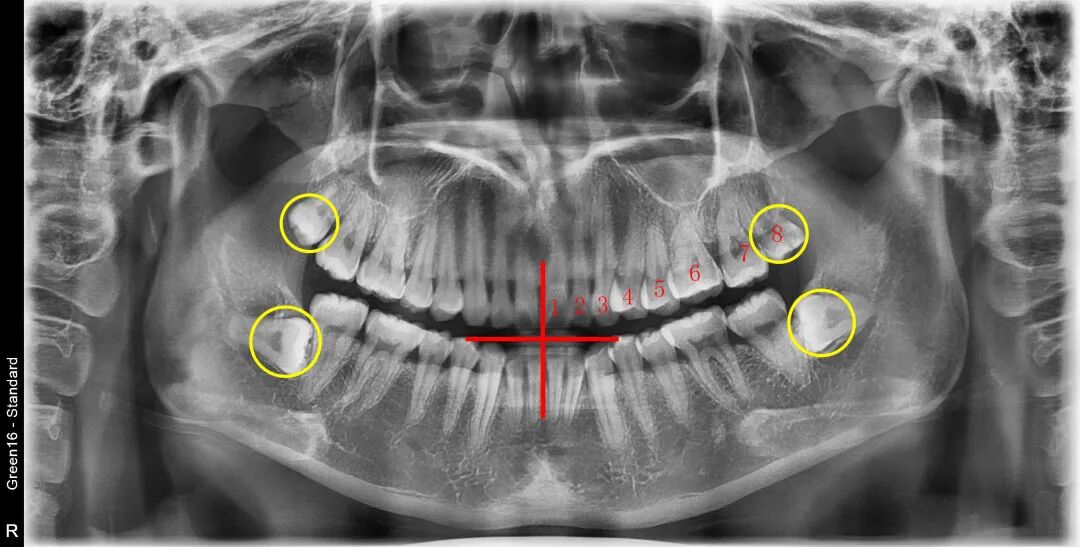

🔎智齿

与其费劲巴拉用舌头舔自己长没长智齿,不如拍片看一下,智齿如果完全埋伏,就舔不到,根本舔不到~

X光拍片为什么要等看牙为什么要拍片?非专业人士如何看懂自己的牙片!_https://www.jmylbn.com_新闻资讯_第8张

△全口牙齿一般有28-32颗,在牙片上从中间牙齿往后数第八颗就是智齿。